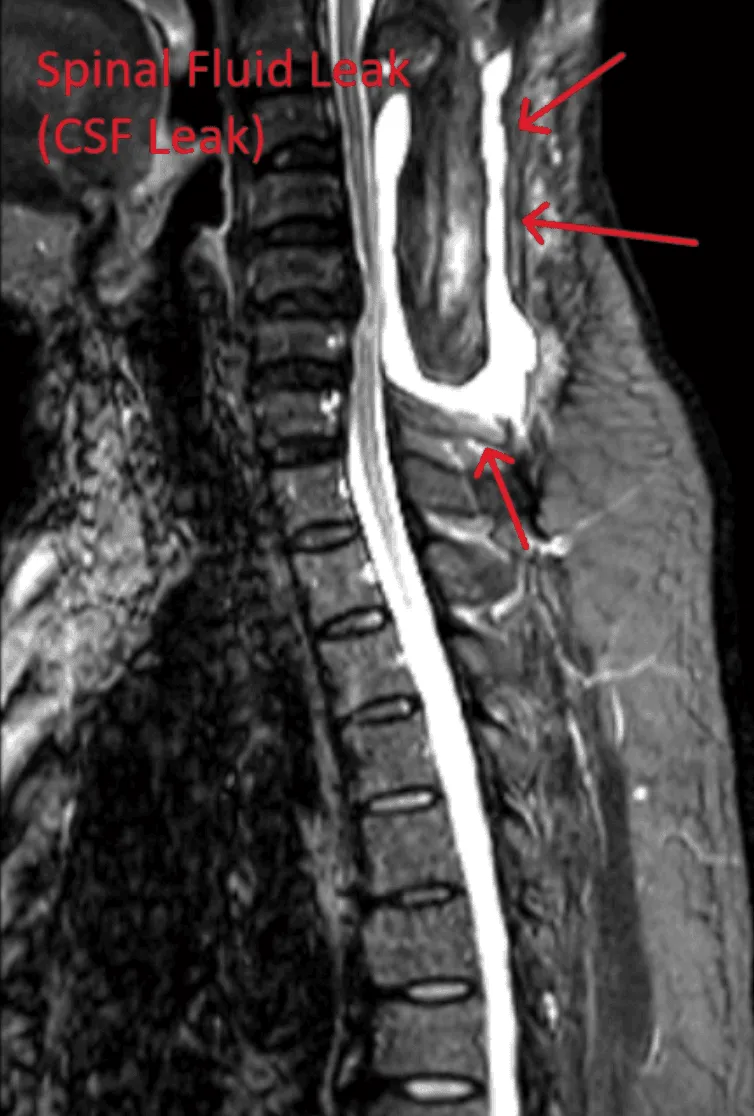

MRI image showing a spinal fluid leak with red arrows pointing to the affected area.

Spinal Fluid Leak

Dural tears leading to cerebrospinal fluid leaks, requiring additional repair surgery.